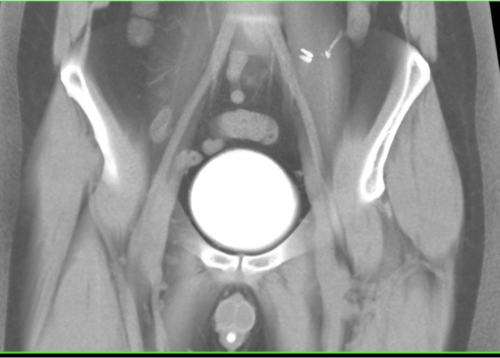

Pelvic fracture

What does this refer to

Open book pelvic fracture

Pelvic Fractures